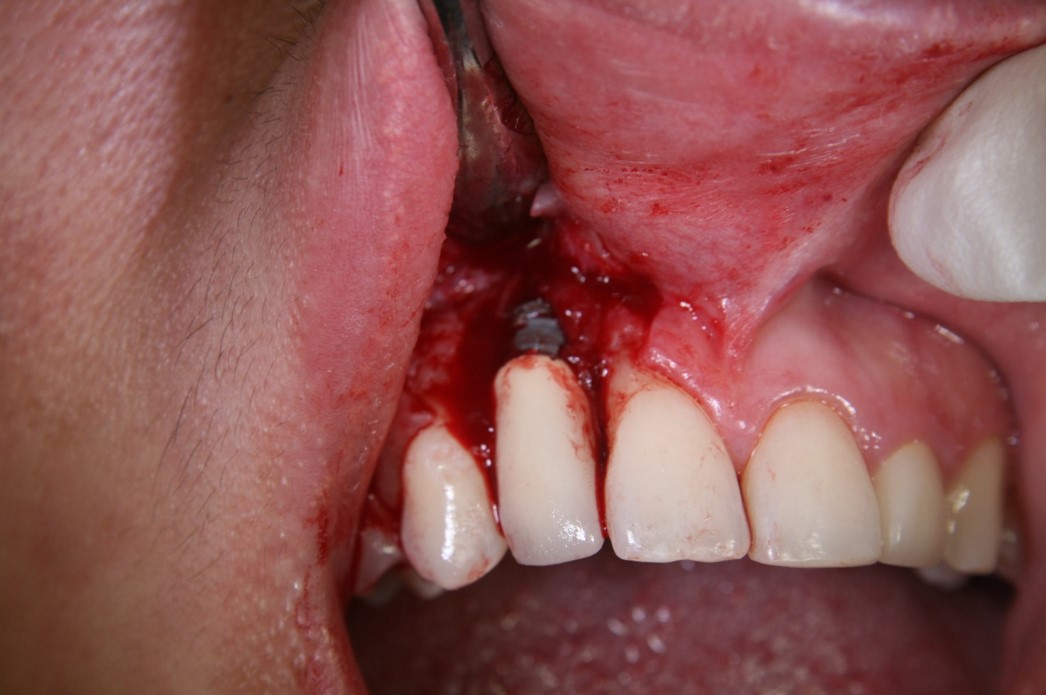

In practice, dentists may encounter a variety of bone defects, including extraction site defects (Figure 1 and Figure 2), fenestrations/dehiscence defects, horizontal ridge deficiencies (Figure 3 and Figure 4), vertical ridge deficiencies, and periodontal defects (Figure 5 through Figure 7).1,2 The most common, however, are extraction site defects that may compromise subsequent implant placement or stability of the ridge when no implant is planned.1,2

Fig 1. Tooth extraction resulted in a defected wall.

Figure 1